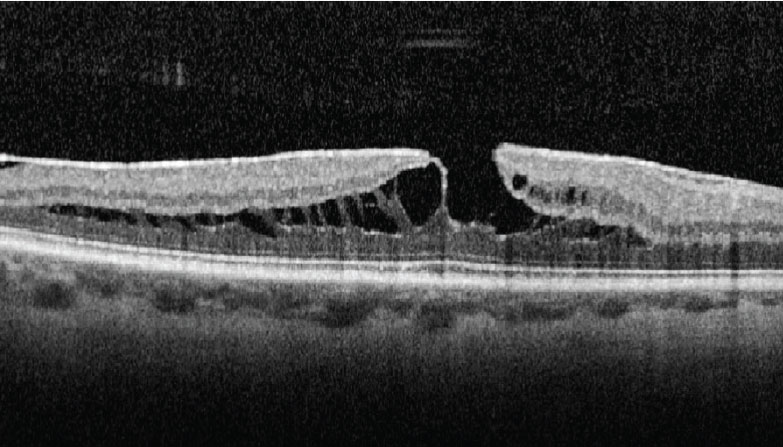

6. Tractional lamellar hole

Tractional lamellar holes (Figure 6) form when the OPL and ONL separate. On OCT, this pattern can be readily identified due to its moustache-like appearance. Tractional lamellar holes are typically observed in eyes with ERM and VMT.9 Vision is generally good despite the presence of tractional lamellar hole,9 likely because the photoreceptor-RPE interface isn’t disturbed.

![]() |

|

Figure 6. Tractional lamellar hole, readily identifiable by its moustache-like appearance. (From: Govetto A, Dacquay Y, Farajzadeh M, et al. Lamellar macular hole: Two distinct clinical entities? Am J Ophthalmol. 2016;164:99-109. Used with permission.) |

7. Degenerative lamellar hole

Several features characterize degenerative lamellar holes (Figure 7), including a central cavitation that may involve the layers of the outer retina, foveal bump, and EZ disruption.

In contrast to the moustache-like appearance of tractional lamellar holes, degenerative lamellar holes have a top-hat like appearance. Most degenerative lamellar holes are also associated with the presence of epiretinal proliferation.9 Similar to tractional lamellar holes, these cases are often observed.

Figure 7. Degenerative lamellar hole, characterized by central cavitation. (From: Govetto A, Dacquay Y, Farajzadeh M, et al. Lamellar macular hole: Two distinct clinical entities? Am J Ophthalmol. 2016;164:99-109. Used with permission.) |